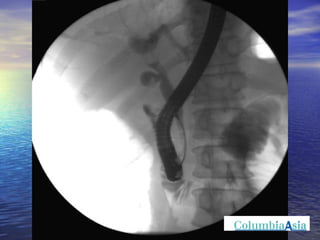

ERCP (Endoscopic Retrograde Cholangio Pancreatography) is an endoscopic procedure used to diagnose and treat issues in the bile and pancreatic ducts. It involves positioning an endoscope and using x-rays to view the ducts while performing procedures like draining bile ducts, removing gallstones, and placing stents. Potential complications include pancreatitis, bleeding, infection, or perforation. Careful pre- and post-procedure steps like monitoring and antibiotics are important to minimize risks.